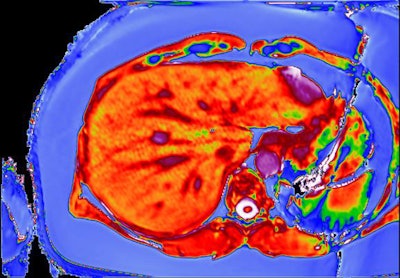

Scanning technology from liver MRI software developer Perspectum Diagnostics could almost halve the number of liver biopsies carried out in people with fatty liver disease, the firm announced.

A new study found that 458 out of every 1,000 liver biopsies could be avoided if people are first assessed using Perspectum Diagnostics' LiverMultiScan software, which reads data from an MRI scan of the liver (Alimentary Pharmacology & Therapeutics, 22 December 2017). This could save approximately 150,000 pounds (169,000 euros) per 1,000 patients.

The study, conducted by researchers at the University of Birmingham and the University of Edinburgh, investigated the performance and cost of multiparametric MRI (LiverMultiScan) alongside existing biomarkers in the assessment of nonalcoholic fatty liver disease (NAFLD). Adult patients undergoing standard-of-care liver biopsy for NAFLD were prospectively recruited at the two U.K. liver centers in Birmingham and Edinburgh, and they underwent multiparametric MRI, blood sampling, and transient elastography within two weeks of liver biopsy. The researchers compared noninvasive markers, with histology as the gold standard.

They found LiverMultiScan in 50 patients and six healthy volunteers was superior for grading disease severity and excluding people at increased risk of disease progression, compared with the other tests evaluated.